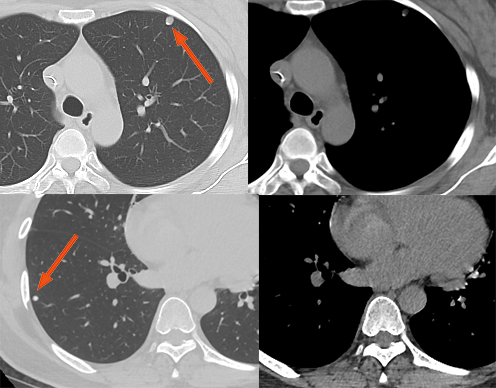

单发肺转移

无恶性肿瘤病史的患者单发肺转移的发生率很低(0.4-9.0%),有恶性肿瘤史的患者发生单发肺结节时 25-46% 为转移,且原发肿瘤多为腺癌或软组织肉瘤等。Cahan 总结 800 例肺孤立性肿物提出以下原则:原发肿瘤为鳞癌时肺内肿物多为原发,为腺癌时肺内原发和转移的概率各半,原发为软组织或骨肉瘤、黑色素瘤时肺内多为转移。CT 上单发转移瘤多数边缘光整,符合转移瘤特点,少数边缘可出现分叶、毛刺等,与原发肿瘤难以鉴别。

直肠癌术后 2 年,发现右肺结节 1 周。双肺仅见 1 枚结节,穿刺活检证实为直肠癌转移。